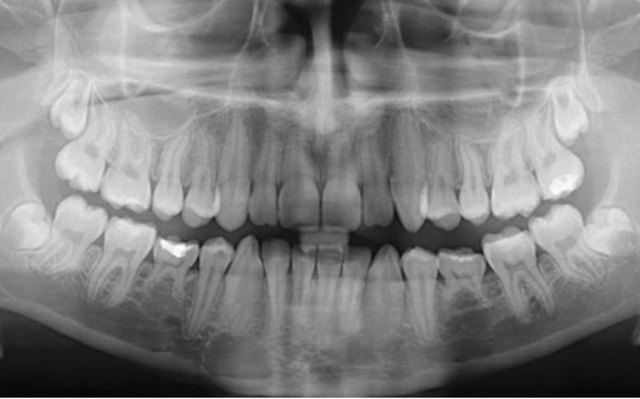

1. Digital X-ray: This new x-ray is faster, and has less radiation than the traditional x-ray.